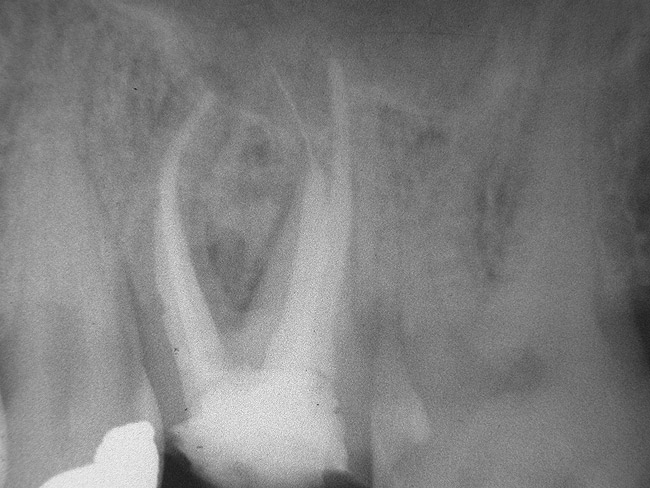

Figure 5a  Tooth No. 30 The preoperative radiograph revealed a periapical radiolucency and transported canals in the mesial root.

Figure 5a

Figure 5b  This procedural error may have delayed the progress of therapy or even made it impossible to thoroughly clean and shape the canal terminus. Root-end surgery was performed to enucleate the periapical pathology and debride previously uncleaned parts of the canals. On the apically resected root surface, an uncleaned portion of 1 canal and an isthmus connecting the 2 main canals became visible under high magnification (Figure 5B), which were prepared to 1 retrocavity using ultrasonic tips (Figure 5C) and filled with MTA (Figure 5D).

Figure 5b